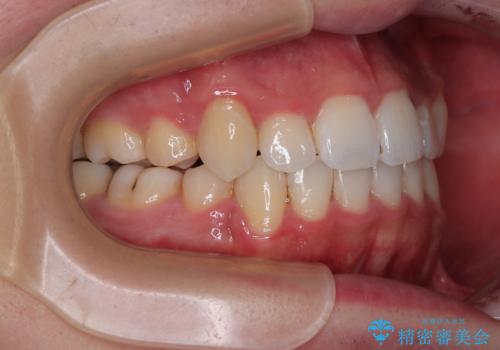

前歯の歯列が整ったことで、歯磨きが大変やりやすくなり、患者様には大変満足していただけました。

上下ともに八重歯が顕著であり、前歯のクロスバイトがあったため、上下左右の第一小臼歯4本を抜歯し、ワイヤー装置での抜歯矯正を行うこととしました。